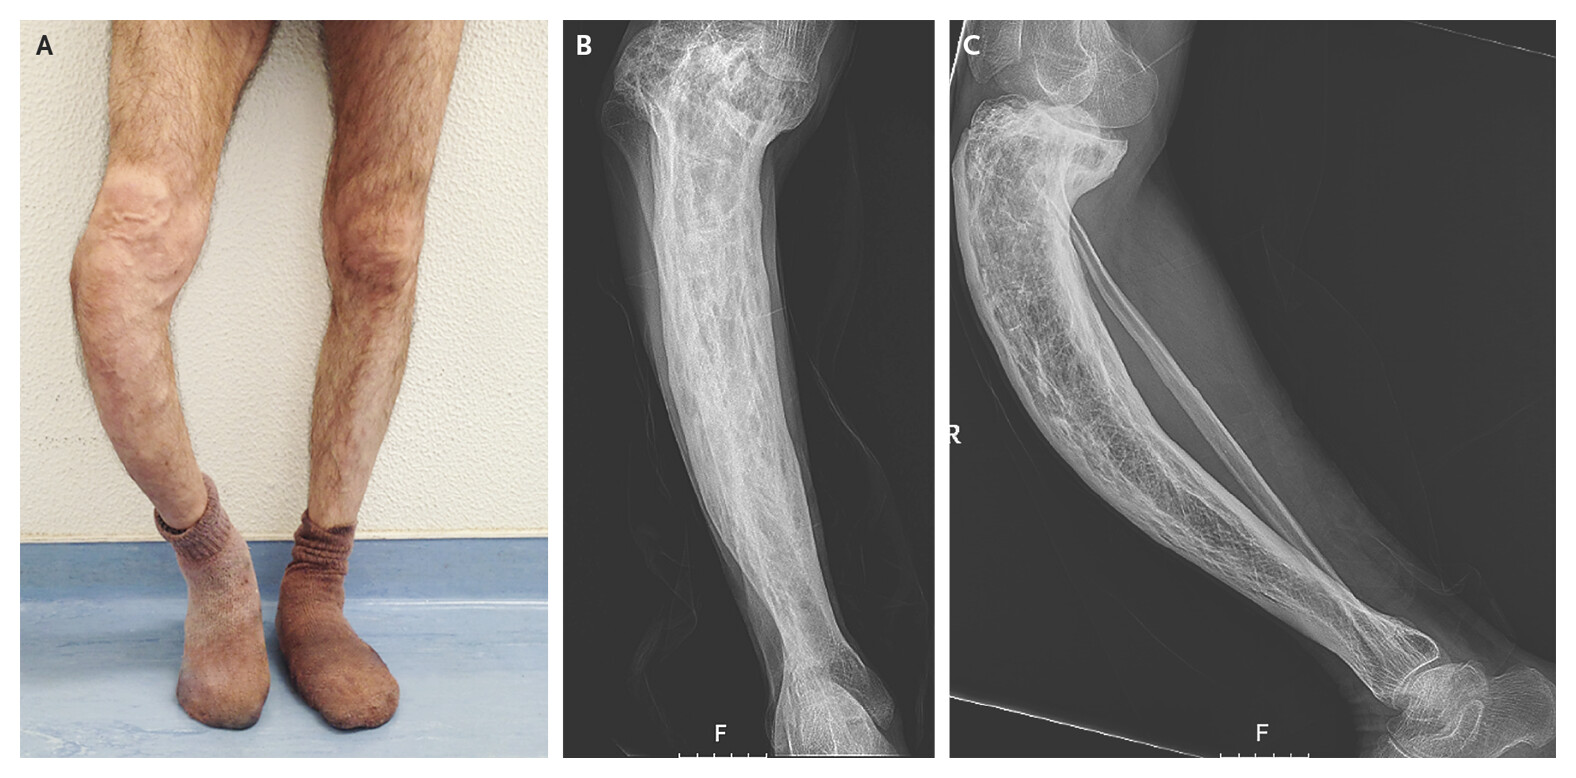

Paget's disease of bone is a chronic disorder that causes abnormal bone remodeling. The bone is broken down and rebuilt more quickly than normal, leading to weakened bones.

- - Bone Pain - Deformities such as enlarged or misshapen bones. - Fractures in weakened bones.

- - Fractures - Arthritis due to joint damage. - Hearing Loss if the skull is involved.